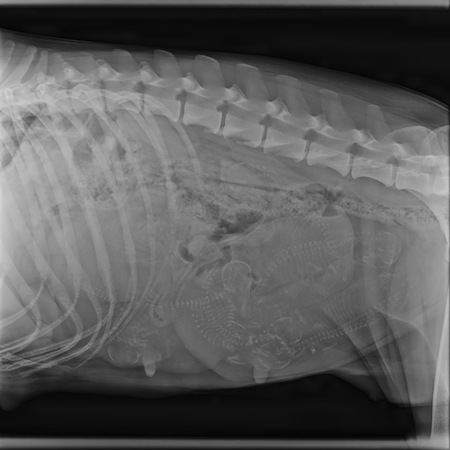

Heute waren wir beim Röntgen, um zu wissen, ob eines der beiden Extreme - besonders großer oder kleiner Wurf - vorliegt.